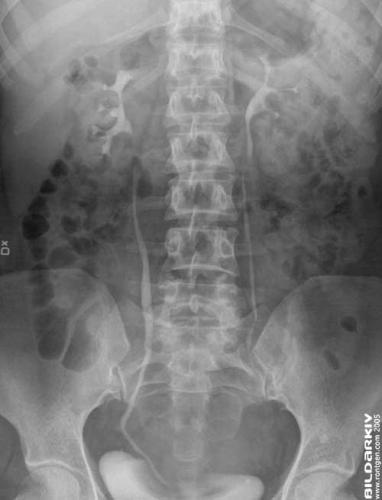

Urografi 6

Frontal bild båda njurarna 5 minuter efter kontrast injektion.